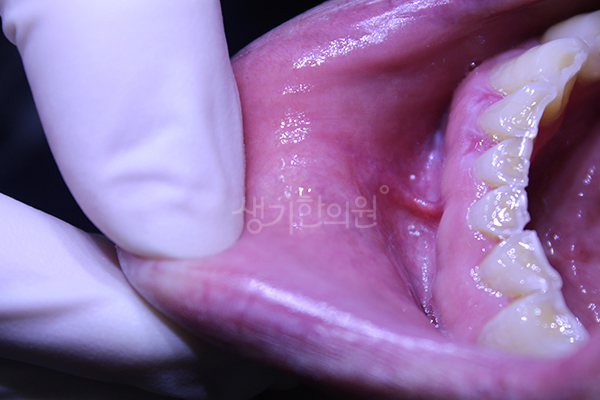

생기 치료 사례는 생기한의원 각 지점별 실제 치료 환자의 동의를 받아 공개하는 내용입니다.

생기 치료 사례는 동일인의 치료 전후 사진을 인위적 수정하지 않은 내용입니다.

각 환자의 상태와 특성에 따라 치료 효과에 차이가 있을 수 있고, 일반적 부작용이 나타날 수 있습니다.

치료 부위의 특성상 공유하지 못한 다양한 생기 치료 사례는 각 지점에서 안내 도와드리겠습니다.